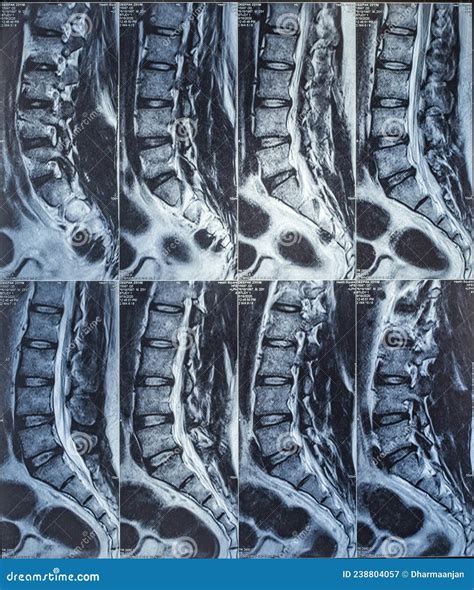

A Lower Back X Ray is a common, non-invasive imaging test that uses a small amount of radiation to create pictures of the lumbar spine. The lumbar spine consists of the five vertebrae in your lower back. By capturing these images, doctors can evaluate the bones, joints, and overall alignment of the lower spine.

Unlike more advanced imaging studies, such as an MRI or CT scan, a plain X-ray focuses primarily on dense structures like bone. While it cannot show soft tissues like nerves, discs, or muscles in great detail, it is highly effective for identifying bone-related problems that often cause chronic pain.

What Can Be Seen on a Lower Back X Ray?

While an X-ray has limitations, it is excellent at highlighting specific issues. The following table summarizes what clinicians look for when reviewing these images:

Condition What the X-Ray Shows

Fractures Disruption or cracks in the vertebrae bone.

Arthritis Narrowed joint spaces or bone spurs (osteophytes).

Scoliosis Abnormal side-to-side curvature of the spine.

Spondylolisthesis One vertebra slipping forward over the one below it.

Infections/Tumors Areas of bone destruction or abnormal bone growth.

It is important to manage expectations regarding what a Lower Back X Ray can do. Because it focuses on bone, it cannot directly visualize spinal discs, spinal nerves, or ligaments. Therefore, an X-ray might appear "normal" even if you are experiencing significant pain, as many back issues are caused by soft tissue problems like a herniated disc or muscle strain.